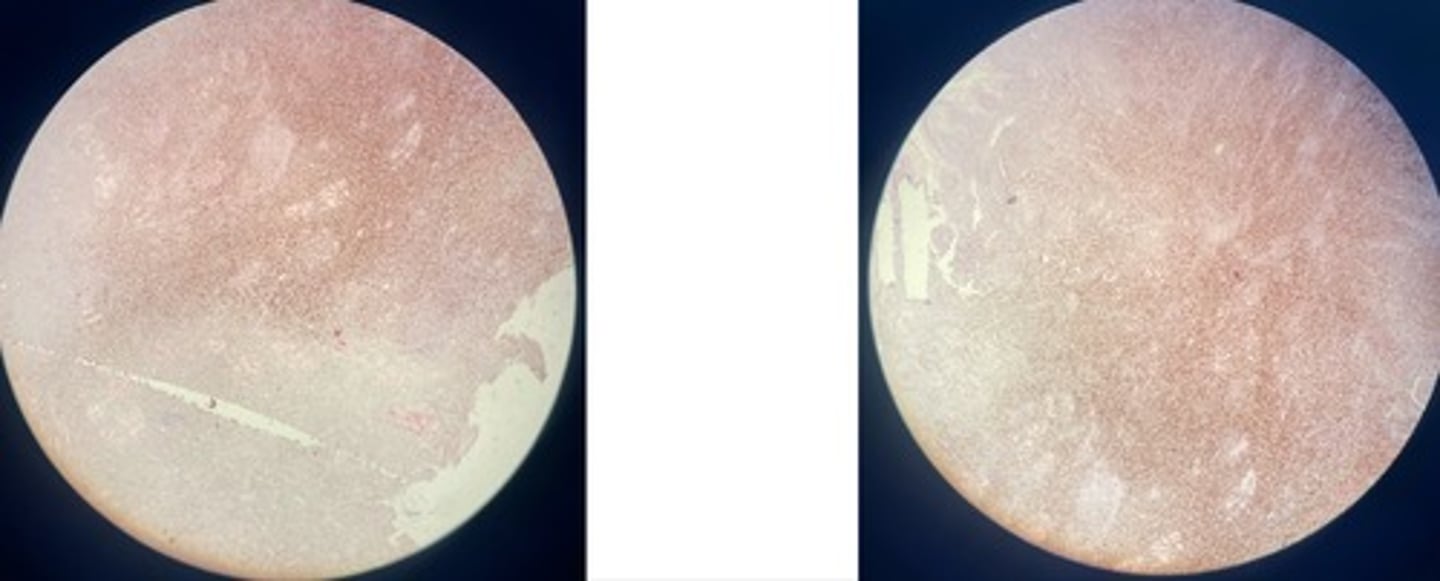

Lymphoma

- many lymphoblasts infiltrating muscle fibres => atrophy + degen

- mitotic figures

Mast cell tumour MCT

- cells in sheets + cords b/w collagen

- deep blue granules in cytoplasm

- round neoplastic cells are mixed w/ eosinophils